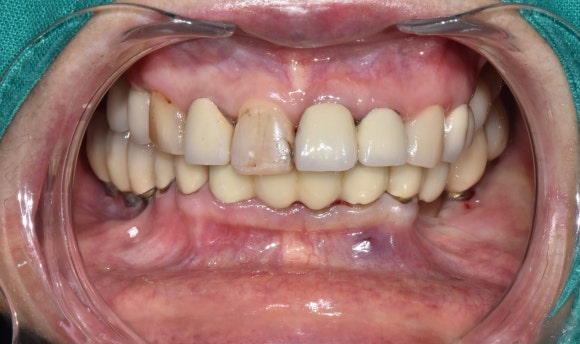

며칠 뒤, 새로운 크라운 장착!

며칠 뒤, 자연치아보다 더 자연스럽고 예쁜 크라운이 완성되어 왔습니다.

빠르게 조치한 덕에 자연치아를 한 번 더 살려서 쓸 수 있게 된 케이스였습니다.

크라운의 끝이 늘 임플란트가 아니라는 것,

이제 모두 아시겠지요? ^^